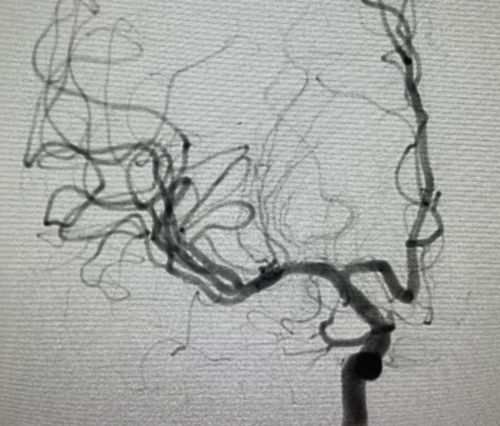

术后,大脑动脉血流恢复。

做完手术,小王原本不能动弹的左手立即就可以抬高。